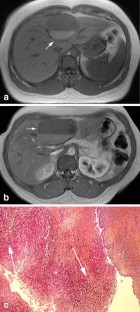

Magnetic resonance imaging (MRI) and magnetic resonance cholangio-pancreatography (MRCP) features were analyzed in the diagnosis of seven surgically resected hepatobiliary cystic tumors with reference to histopathological data. Homogeneity, size, location, signal intensity, presence or absence of septa and/or nodules and MRCP features of the lesions were studied. Histological evidence demonstrated six biliary cystadenoma (BCA) including four pseudo-ovarian stroma (POS) and one biliary cystadenocarcinoma (BCAC). Cystic lesions (3–15 cm in diameter) were homogeneous in the six BCA, heterogeneous in the one BCAC, and were located in the left and right liver, respectively. On T2-weighted images all lesions were hyperintense. On T1-weighted images hypointensity was found in three BCA (all serous fluid, including one POS), isointensity was found in the three others (two mucinous and one hemorrhagic fluid, including three POS) and in the one BCAC (containing mucinous fluid). Septas were present in all cases and nodules only in the one BCAC. On MRCP a hyperintense cystic lesion was found in all cases and a bile ducts dilatation in two BCA and the one BCAC. Gadolinium-enhanced MRI in combination with MRCP is a valuable tool for the diagnosis of BCA or BCAC. However, no specific information is gained for POS detection.

Fig. 3